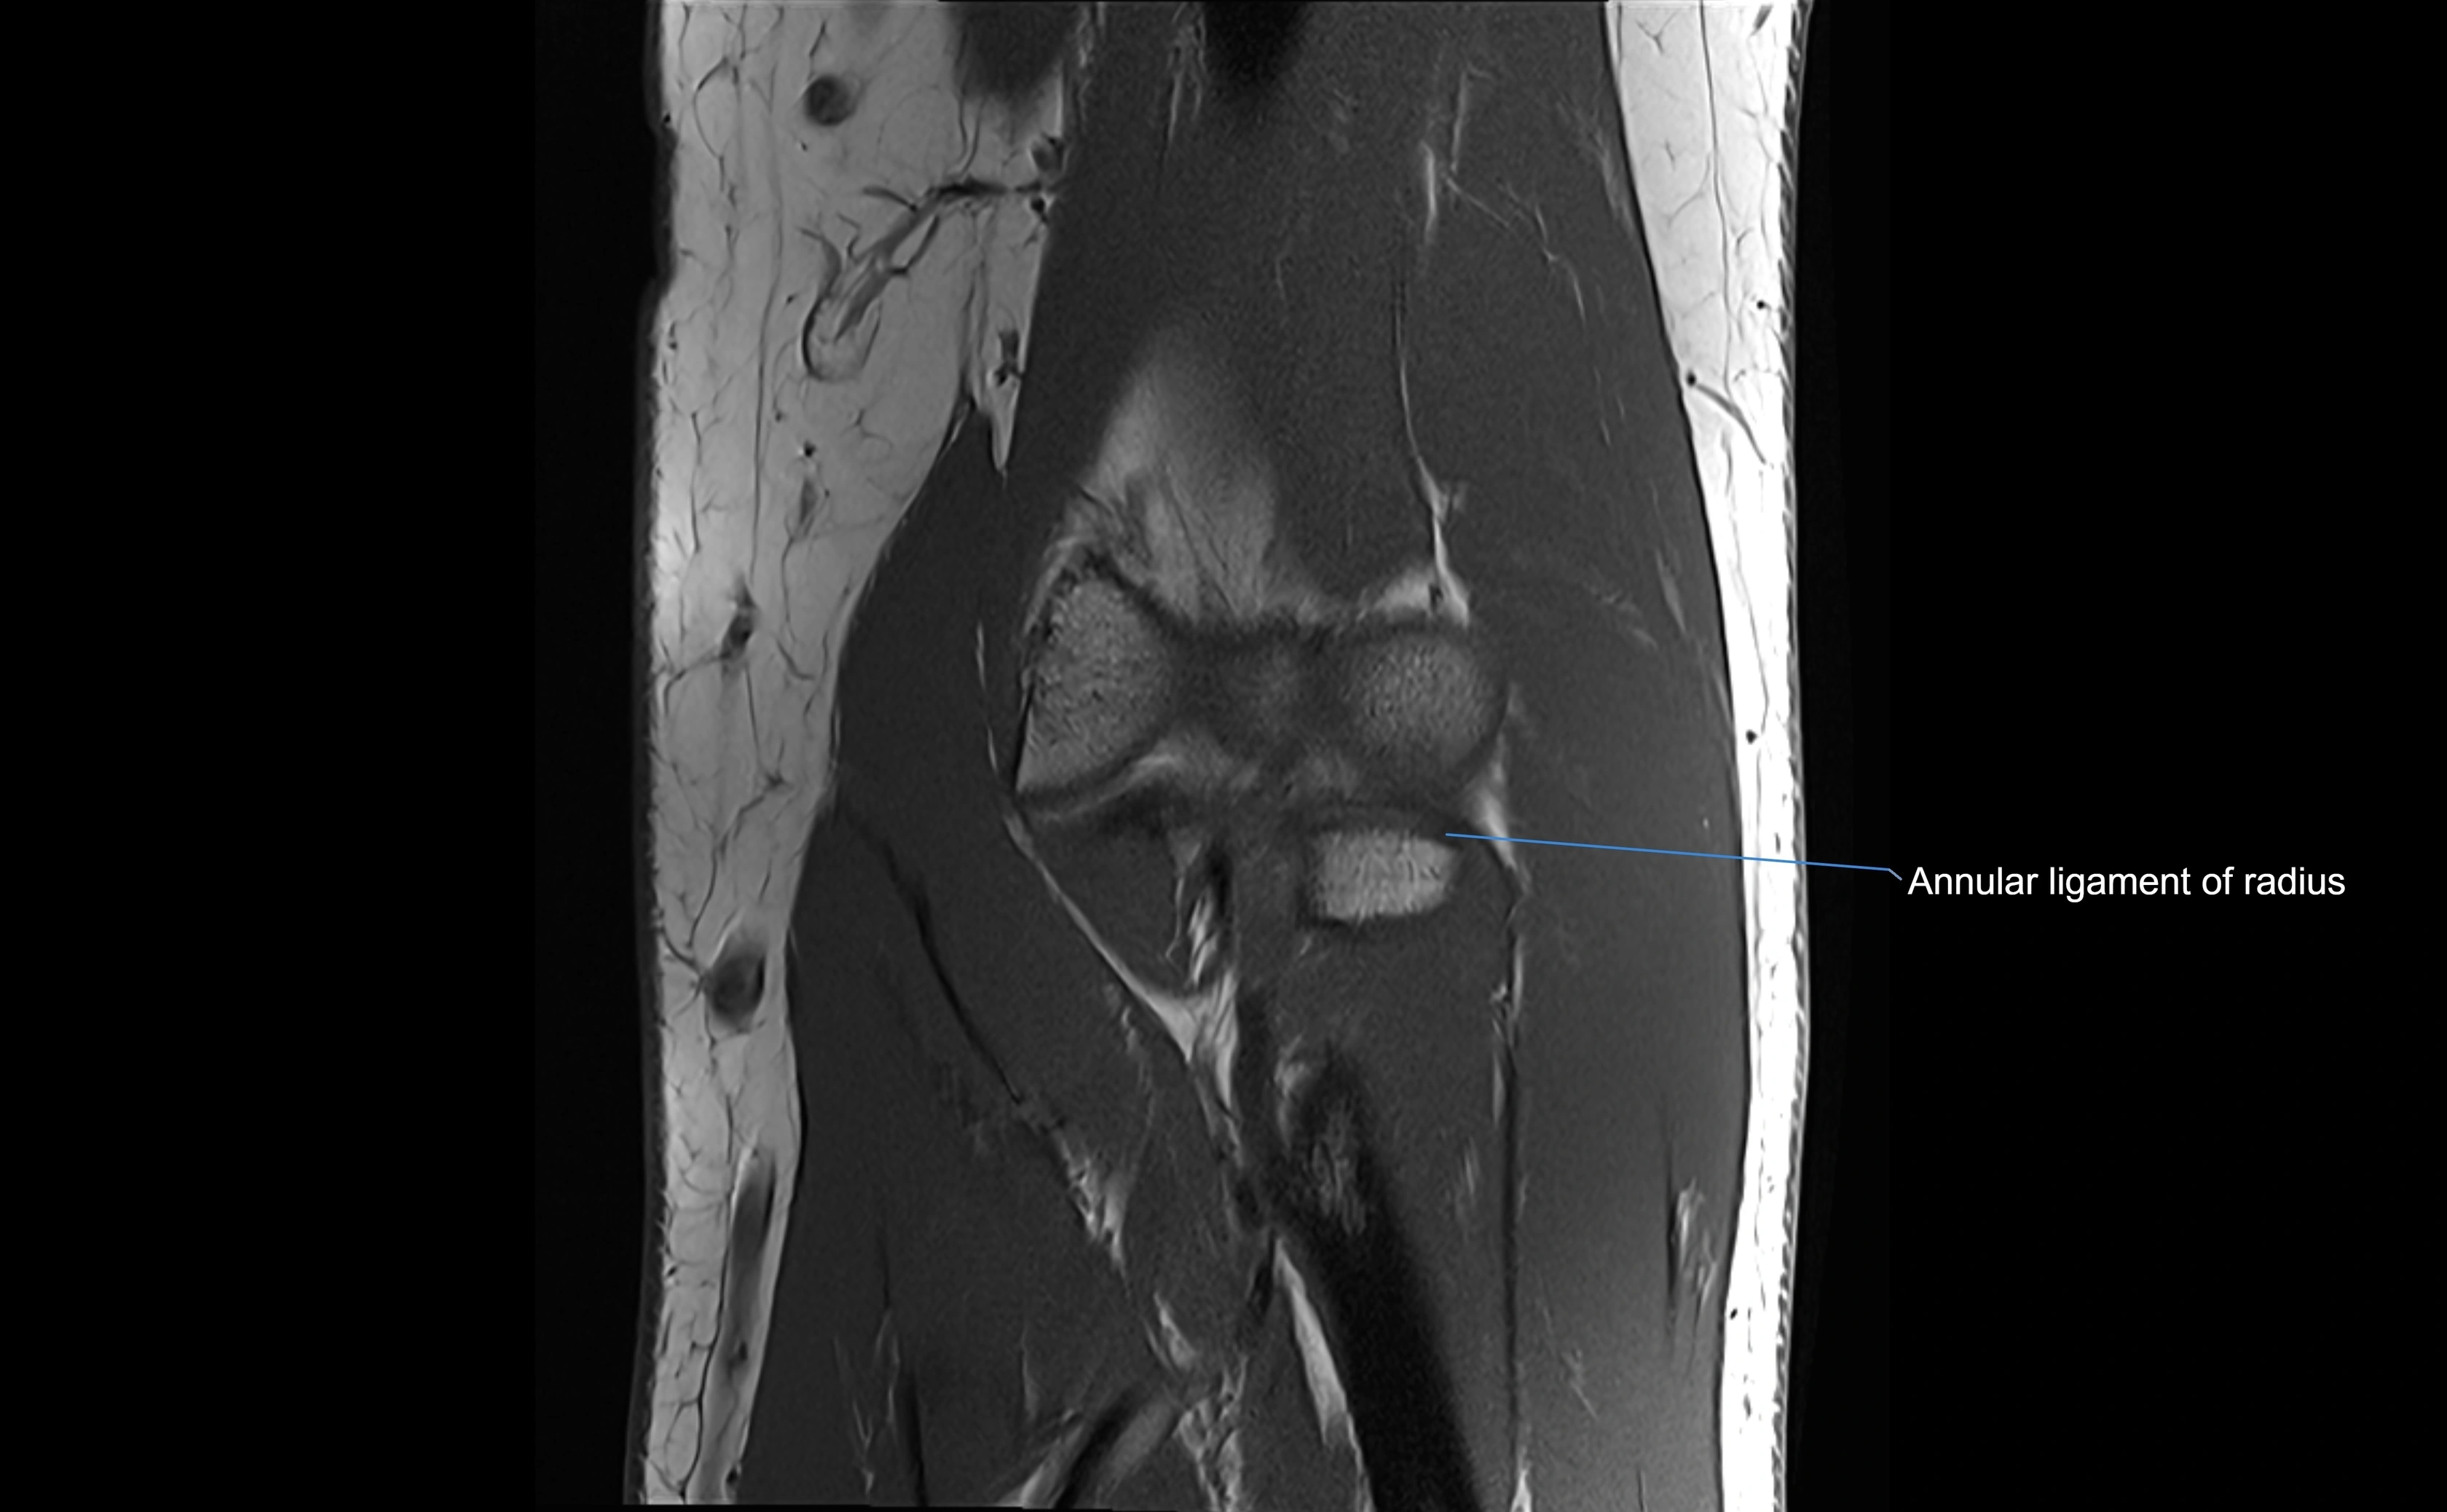

MRI Appearance

T1-weighted images:

• Ligament: low signal intensity (dark), appearing as a continuous band around the radial head.

• Adjacent fat and marrow: bright, creating contrast with the ligament.

• Thickening or disruption indicates injury or fibrosis.

• Joint capsule and synovium seen as thin low-signal lines contiguous with ligament margins.

T2-weighted images:

• Ligament: low signal (dark) with clear delineation from joint fluid.

• Fluid or edema: bright hyperintense, separating or surrounding the ligament in partial tears.

• Complete tear: discontinuity or non-visualization of ligament fibers, often with joint effusion.

STIR:

• Normal ligament: dark band encircling radial head.

• Pathology: bright hyperintense periligamentous signal suggesting edema, sprain, or partial tear.

Proton Density Fat-Saturated (PD FS):

• Normal: dark, well-defined band outlining the radial head.

• Partial tear: irregular or bright hyperintense signal within or adjacent to ligament fibers.

• Joint effusion and reactive synovitis appear bright and are well visualized.